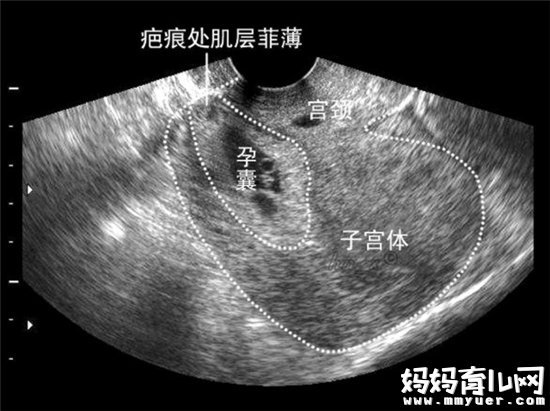

原来刘女士第一胎宝宝是剖腹产方式出生的,子宫上留有瘢痕,而这次二胎受精卵着床刚好在瘢痕上,引起了出血,如果让孩子继续长下去,她就要面临子宫破裂大出血,甚至必须切除子宫的风险,再加上刘女士本身就属于比较危险的高龄孕妇,无奈之下,她只能忍痛割爱,在医生的建议下终止了妊娠。

剖腹产时医生会在子宫上切开小口,取出宝宝后再缝合,子宫上就留下了瘢痕,这个地方常常有微小的裂隙,宫腔和黏膜层不完整,肌肉层之间还有缝隙。

如果再次怀孕后,受精卵碰巧在这个瘢痕附近着床,不断生长后会把肌肉层撕开,很容易导致大出血及孕晚期的子宫破裂,是比较难处理的异常妊娠。